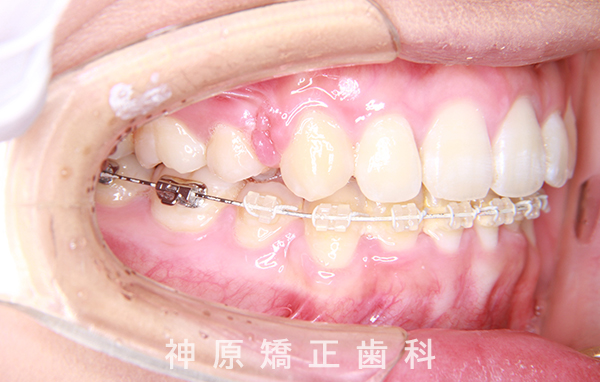

治療経過1年後